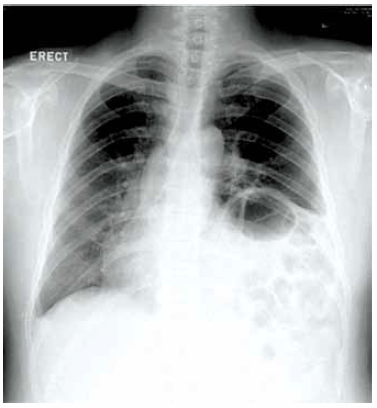

Homem de 73 anos, atendido em hospital após acidente automobilístico (condutor), apresentando contusões e escoriações na parede torácica e abdominal, encontra-se ansioso e agitado, com PA 110 x 75 mmHg, pulso 92 bpm, FR 24 irpm e saturação de oxigênio de 89%. Relata falta de ar e dor à palpação do abdome. No exame físico, o murmúrio vesicular está diminuído em base esquerda. RX tórax a seguir.

Com base na história clínica e nos dados do exame físico apresentados, a conduta a ser realizada ao paciente e a hipótese diagnóstica são, respectivamente: